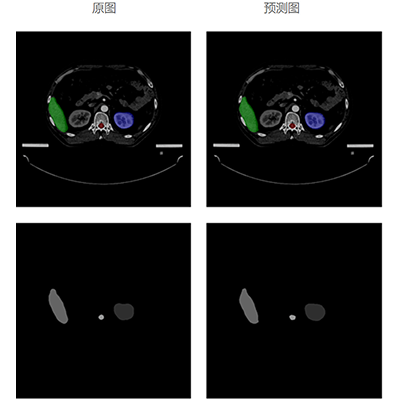

自动勾画效果